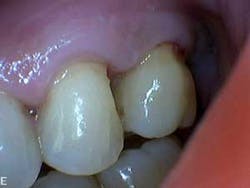

Dental examination revealed gingival swelling and bleeding on probing. Periodontal probing showed moderate-to-deep pocket depths in all posterior teeth (figures 1–3). Generalized bone loss was observed on radiographs (figures 4–6). Tooth vitality and percussion tests were negative. Teeth 2, 3, 31, 14, and 15 had Class III mobility. The patient was diagnosed with Type IV chronic adult periodontitis. Treatment options were discussed, and, after explanation, the patient agreed to the LANAP procedure.

Patient presentation before LANAP treatment (figures 1–6)